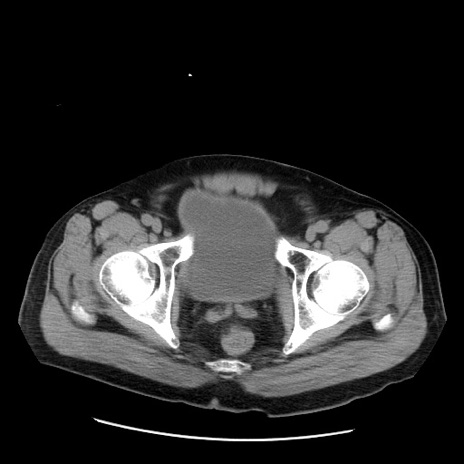

症例20(横断像)

【症例】 60歳代男性

【主訴】 腹部膨満、嘔吐

【現病歴】5日前頃より倦怠感を認め食事量減少し4日前の朝嘔吐、食事摂取困難となった。 3日前近医受診し点滴施行され整腸剤などを処方された。 当日他院を受診し、腹部膨満著明、炎症反応の上昇(CRP10.8、WBC11200)あり、紹介受診となる。

【身体所見】 意識JCS1 受け答えがはっきりしないBP 111/57mHg、 P 67bpm、、BT35.2°C、SpO2 97%(RA)、 腹部:膨隆、打診で鼓音あり、全体的に圧痛有り、腸蠕動音(-)、反跳痛ははっきりせず。

【データ】WBC 11400、CRP 14.20